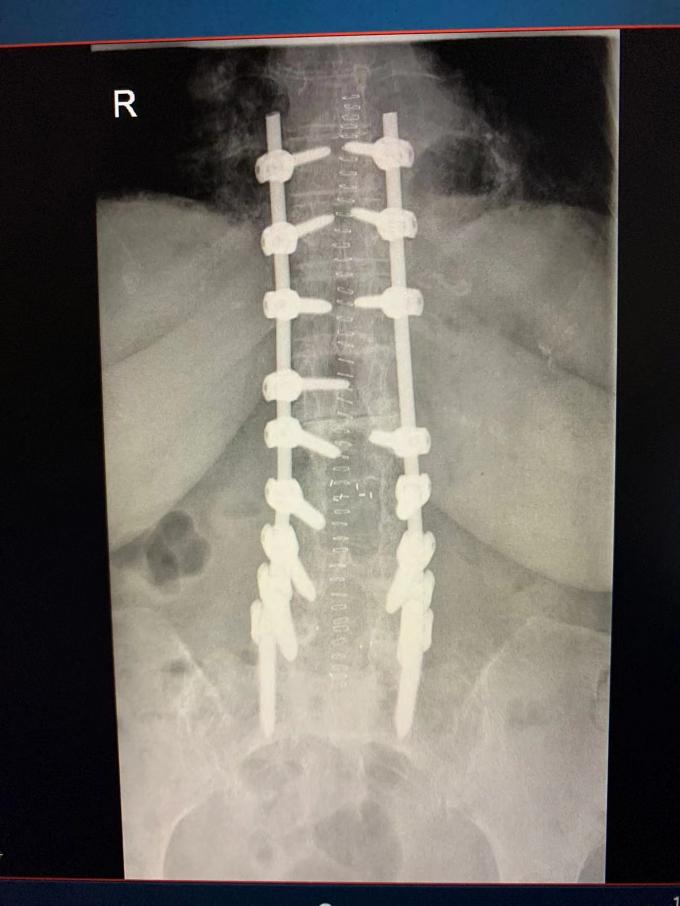

Dieses Mal, haben wir einen anderen Fall spinaler Schraubenchirurgie geholt. Das Bild zeigt den Röntgenstrahl nach der erfolgreichen Operation. Es kann dass, nach der Anwendung unseres spinalen Schraubenstangensystems gesehen werden, der Dorn des Patienten tadellos geregelt worden ist. Ein großes danken Ihnen zu unserem orthopädischen Doktor, der perfekt war.